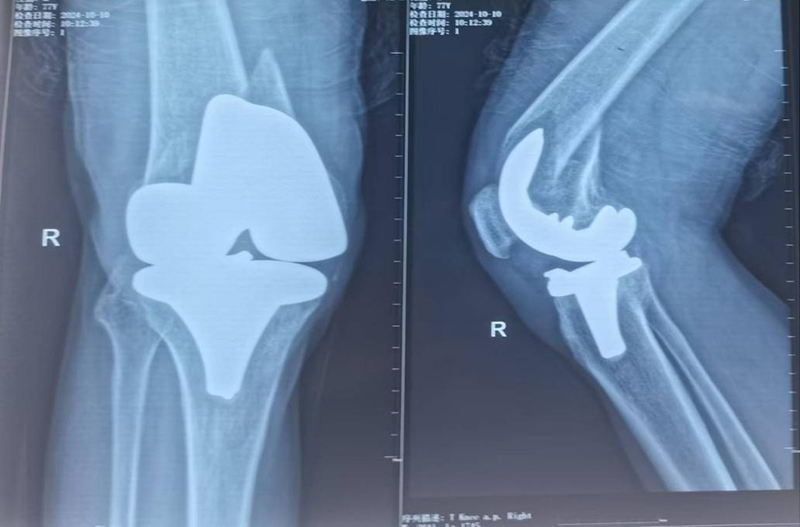

膝关节置换术后假体周围骨折,假体松动

手术由骨科专家许立新主任亲自主刀,在手麻科医护人员的全力配合下,顺利开展。手术过程中,发现膝关节假体彻底松动,胫骨假体也发生了松动,这再次证实了术前计划的合理性,去除松动假体后,安装特制肿瘤膝关节,手术过程非常顺利,仅用时86分钟。